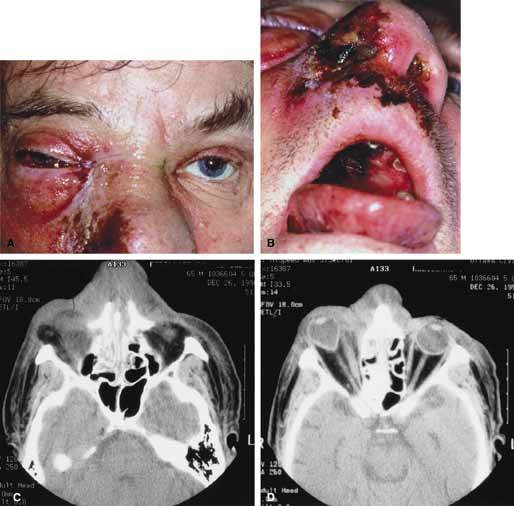

Orbital hemorrhage develops most often as a result of accidental or surgical trauma (Fig. 7A, 7B, and 7C). It has been known to occur during or after a variety of periocular procedures including blepharoplasty, retrobulbar injection, fine-needle biopsy of the orbit, repair of orbital fractures, sinus surgery, dacryocystorhinostomy, lacrimal gland surgery and others.57–61 Spontaneous orbital hemorrhage is uncommon but may occur in patients with lymphangioma (Fig. 8A), orbital varices, leukemia, hemophilia, scurvy, hypertension, aneurysm of the ophthalmic artery, use of thrombolytic agents, labor and delivery etc.62–66 Orbital hemorrhage may also occur spontaneously after a Valsalva maneuver or other straining effort.62,67,68 Another important but more rare cause of spontaneous orbital hemorrhage is a postoperative hemorrhage that occurs approximately 3 to 4 days after orbital surgery. The hemorrhage may be caused by dissolution of intravascular clots. In part it may be related to postoperative inflammation or the release of proteolytic enzymes that results from damage to the orbital fat.59

Fig. 7 A. A 20-year-old male presented to the emergency department after a knife attack with bilateral periocular hemorrhages, ptosis, and proptosis of the left eye; normal vision on the right; and a vision of 20/200 on the left. Both globes were intact. B. Axial computed tomography (CT) scan with signs of orbital hemorrhage bilaterally (Lt > Rt). C. Axial computed tomography (CT) scan with signs of orbital hemorrhage bilaterally (Lt > Rt).

Trauma is one of the numerous causes of orbital hemorrhage. Hemorrhage may be localized and of little consequence, diffuse or subperiosteal and compromise optic nerve function.100–102 Management is dependent on the extent of visual compromise. Orbital hemorrhage without visual compromise will resolve without treatment. Accumulation of blood within the confined orbital space may also form a hematoma. Orbital hematomas can be classified as intraorbital or subperiosteal. Intraorbital hematomas are more common and include the characteristic findings of lid ecchymosis, lid edema, axial globe displacement, diffuse subconjunctival hemorrhage, restricted ocular motility, and varying degrees of visual dysfunction (Fig. 7A, 7B, and 7C). Subperiosteal hematomas are less common and the characteristic findings include proptosis, downward globe displacement, lid ecchymosis, motility impairment, and varying degrees of visual dysfunction. Subperiosteal hematomas most often occur acutely after orbital trauma but may also present days later (Fig. 15A, 15B, and 15C). They more commonly involve the roof and are secondary to rupture of the subperiosteal blood vessels or extrusion of a subgaleal hematoma with subsequent accumulation of blood between the underlying bone and periosteum.104 Nontraumatic subperiosteal orbital hemorrhages (i.e., spontaneous, after straining, vomiting, childbirth, scuba diving, etc.) may also occur, although uncommon.62,63 Similar to the traumatic ones they more commonly occur superiorly.

Fig. 15 A. A 19-year-old university student fell 10–15 feet from a parking garage. While in the emergency department he developed eyelid ecchymosis and reduced visual acuity of the left eye. B. Axial computed tomography (CT) scans revealed a subperiosteal hematoma posteriorly along the medial orbital wall. The blood was drained and postoperatively the acuity returned to 20/20. C. Axial computed tomography (CT) scans revealed a subperiosteal hematoma posteriorly along the medial orbital wall. The blood was drained and postoperatively the acuity returned to 20/20.